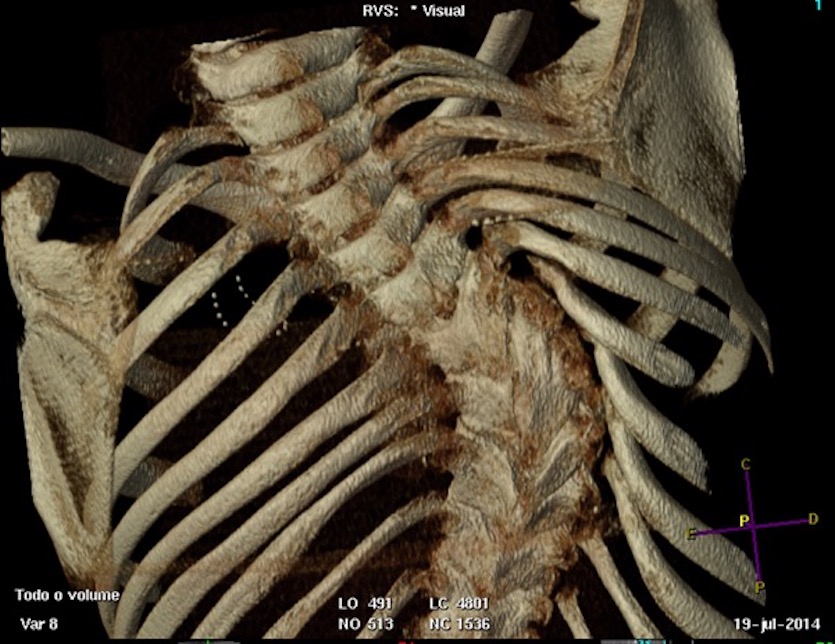

Escoliose congênita se refere a deformidades tridimensionais da coluna devido a alterações da formação vertebral, segmentação vertebral ou suas combinações que surgem devido ao desenvolvimento vertebral anormal durante a quarta a sexta semanas de gestação1,2. Essas deformidades podem ser benignas até incrivelmente complexas (Figura 1). A incidência estimada da escoliose congênita é de 1 em 1000 crianças, contudo esse número pode estar subestimado porque inúmeras crianças são assintomáticas e não tem ciência de possuir anormalidades em suas colunas1-2.

Figura 1. Escoliose Congênita

Tomografias computadorizadas também podem ser utilizadas para se visualizar com maior clareza aspectos morfológicos ósseos relacionados a deformidade na coluna e são de grande utilidade no planejamento cirúrgico6. Contudo, especial atenção é requerida devido a elevada dose de radiação, especialmente em crianças.